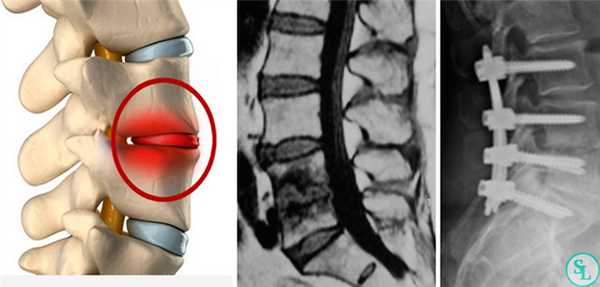

Целями оперативного вмешательства являются ликвидация инфекционного очага, взятие биопсии для микробиологического и гистологического исследования, декомпрессия позвоночного канала со стабилизацией и восстановлением поврежденных спинальных структур

Дискэктомия (удаление разрушенного диска) и корпэктомия (удаление фрагмента тела позвонка) позволяют полностью очистить пораженные ткани. Внедрение распорочных трансплантатов (вырезанных из костных структур, взятых в ребрах или гребне подвздошной кости) позволяет хрящевым тканям начать восстанавливаться, а фиксирующие позвоночный столб титановые конструкции временно снимут нагрузку на пострадавшие позвонки. Реабилитация занимает от 3 месяцев до полугода.

Хирургическое лечение спондилодисцита может проходить в один или два этапа. Если имеется неврологический дефицит, должна проводиться неотложная декомпрессия и стабилизация позвоночника, так как динамика развития неврологических осложнений зависит от быстроты хирургического вмешательства.